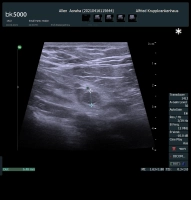

If an appendix/residual appendix is detected sonographically after 6-8 weeks, an interval appendectomy should be performed. According to current literature (Li et al.: Effect of delay to operation on outcomes in patients with acute appendicitis: a systematic review and meta-analysis. J Gastrointest Surg 2019; van Dijk et al.: Meta-analysis of in-hospital delay before surgery as a risk factor for complications in patients with acute appendicitis. Br J Surg 2018; Cameron et al.: Time to appendectomy for acute appendicitis: A systematic review. J Pediatr Surg 2018; 53: 396–405), an appendectomy under antibiotic therapy can be delayed 12-24 hours from diagnosis without increasing the perforation rate. Exceptions exist for patients over 65 years or with relevant comorbidities, especially immunosuppression and immunodeficiency, where early surgery should be performed and a time interval of 12 hours should not be exceeded. The same applies to children and adolescents.